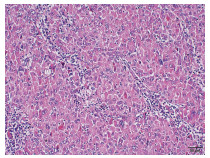

Lymphoepithelioma-like hepatocellular carcinoma: A case report

Xiaotong QIU, Zhengqi WU, Xuxiang XIA, Guoyue LYU

2022, 38(3): 634-635. DOI: 10.3969/j.issn.1001-5256.2022.03.027

Abstract(684) HTML (892) PDF (2924KB)(46)

Abstract: